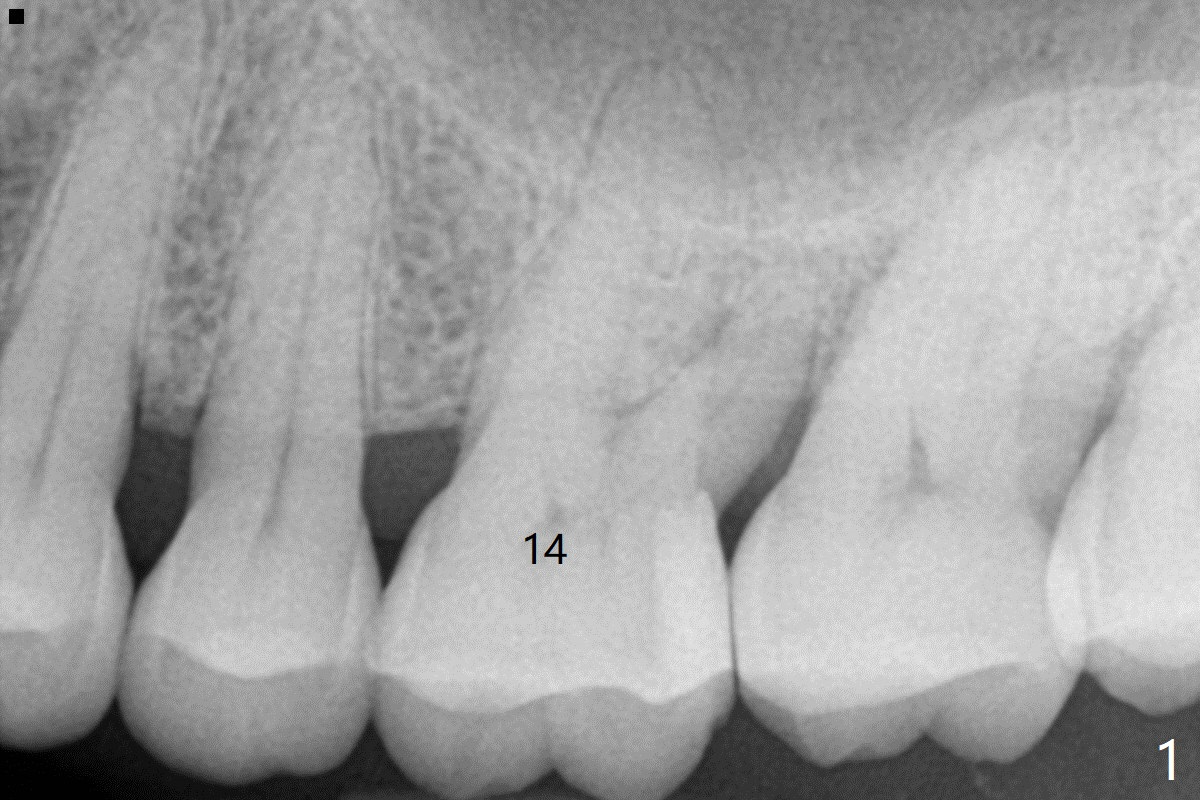

A 65-year-old man had crack tooth syndrome at #14 one month earlier (Fig.1). He shows up with crack and pain in an emergency manner (Fig.2 arrowheads). Preop CT confirms 4.5 mm bone height (Fig.3). Osteotomy will be initiated in the middle of the septum between 3 sockets (Fig.4). Depth of osteotomy is controlled with drill stoppers. After sequential osteotomy free hand, a 5x11 mm tap is used to break through the sinus floor (Fig.5) and sinus lift with Vanilla allograft. To prevent abutment screw loosening, a 5x11 mm tissue-level implant is placed; the distal thread is equicrestal (Fig.6 arrowhead). Following deeper placement of the implant (Fig.7 arrow) with a larger and longer abutment (as compared to that in Fig.6), the margin for an immediate provisional (Fig.9 white curved lines) is prepared in the coronal end of the implant (Fig.8 between arrowheads). With the tissue-level implant, the crown/implant ratio improves. Stress will be partially acting on the implant so that there is less likelihood of abutment screw loosening. The socket heals 1 month postop (Fig.10). The rough surface of the implant is exposed ~ 1 mm. With the margin modified and polished, the provisional returns to place with oral hygiene instruction. It is hoped that the gingiva will cover the exposed rough surface. The buccal rough surface remains exposed 5 months postop (Fig.11). The bone in sinus lift is mature 5 months postop (Fig.12,13). The first 1-2 implant threads are expected to be filled with mature bone in the near future (*). Since the abutment seems long enough for retention, temp bond is used for cementation (Fig.14). Water pik is being applied.